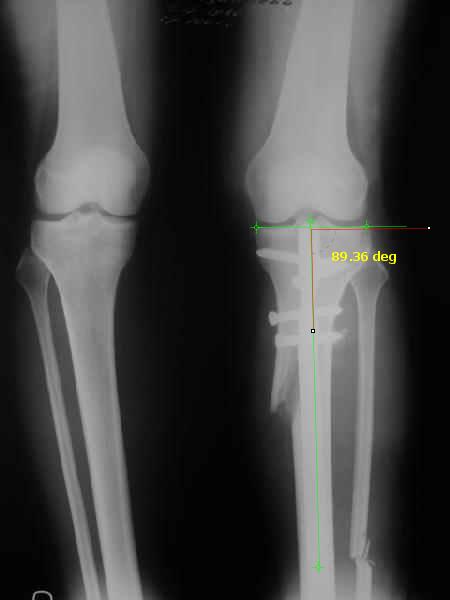

Отправитель: T. Derek V. Cooke 13 Сентябрь 2005, 23:51

|

Hello Alex:

Thanks for the clinical photo.

Your patient appears to have "Insquinting Knees"?

I am attaching a word doc with a 'print screen' of the program in use, showing the images being viewed and analysed

. On the right leg you can see some of the tools (from the tool bar above) applied to demonstrate a mild mech-axis varus of about 5 degrees.

On the left the bone landmarks used in the anlaysis are shown.

The data for the analysis are in the XLs sheet below, exported from the program automatically.

I have given a label of the abreviations and some normative values.

In essence she has a mild mech-axis varus of 7 degrees with some contribution from the femur (2) degrees and more from the tibia (6 degrees), none from the joint.

The analysis took about 6 mins.

Regards

Derek

Отправитель: Alexander Chelnokov 14 Сентябрь 2005, 00:00

TDVC> Your patient appears to have "Insquinting Knees"?

Exactly.

TDVC> In essence she has a mild mech-axis varus of 7 degrees

TDVC> with some contribution from the femur (2) degrees and more from

TDVC> the tibia (6 degrees), none from the joint.

And what is conclusion? Should it be corrected, by what means, at what level, to what axis, with what lateral/medial translation?

Can the attached result be analyzed by the software?